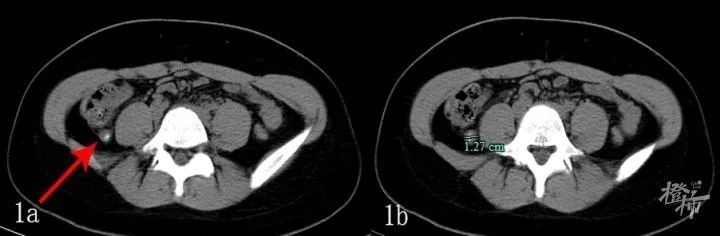

【 医生|24岁姑娘要割阑尾,医生用一根“管子”救了她】下腹部CT平扫:1a示肿大的阑尾,腔内可见粪石(红箭头),1b示阑尾管径明显增宽至1.27cm